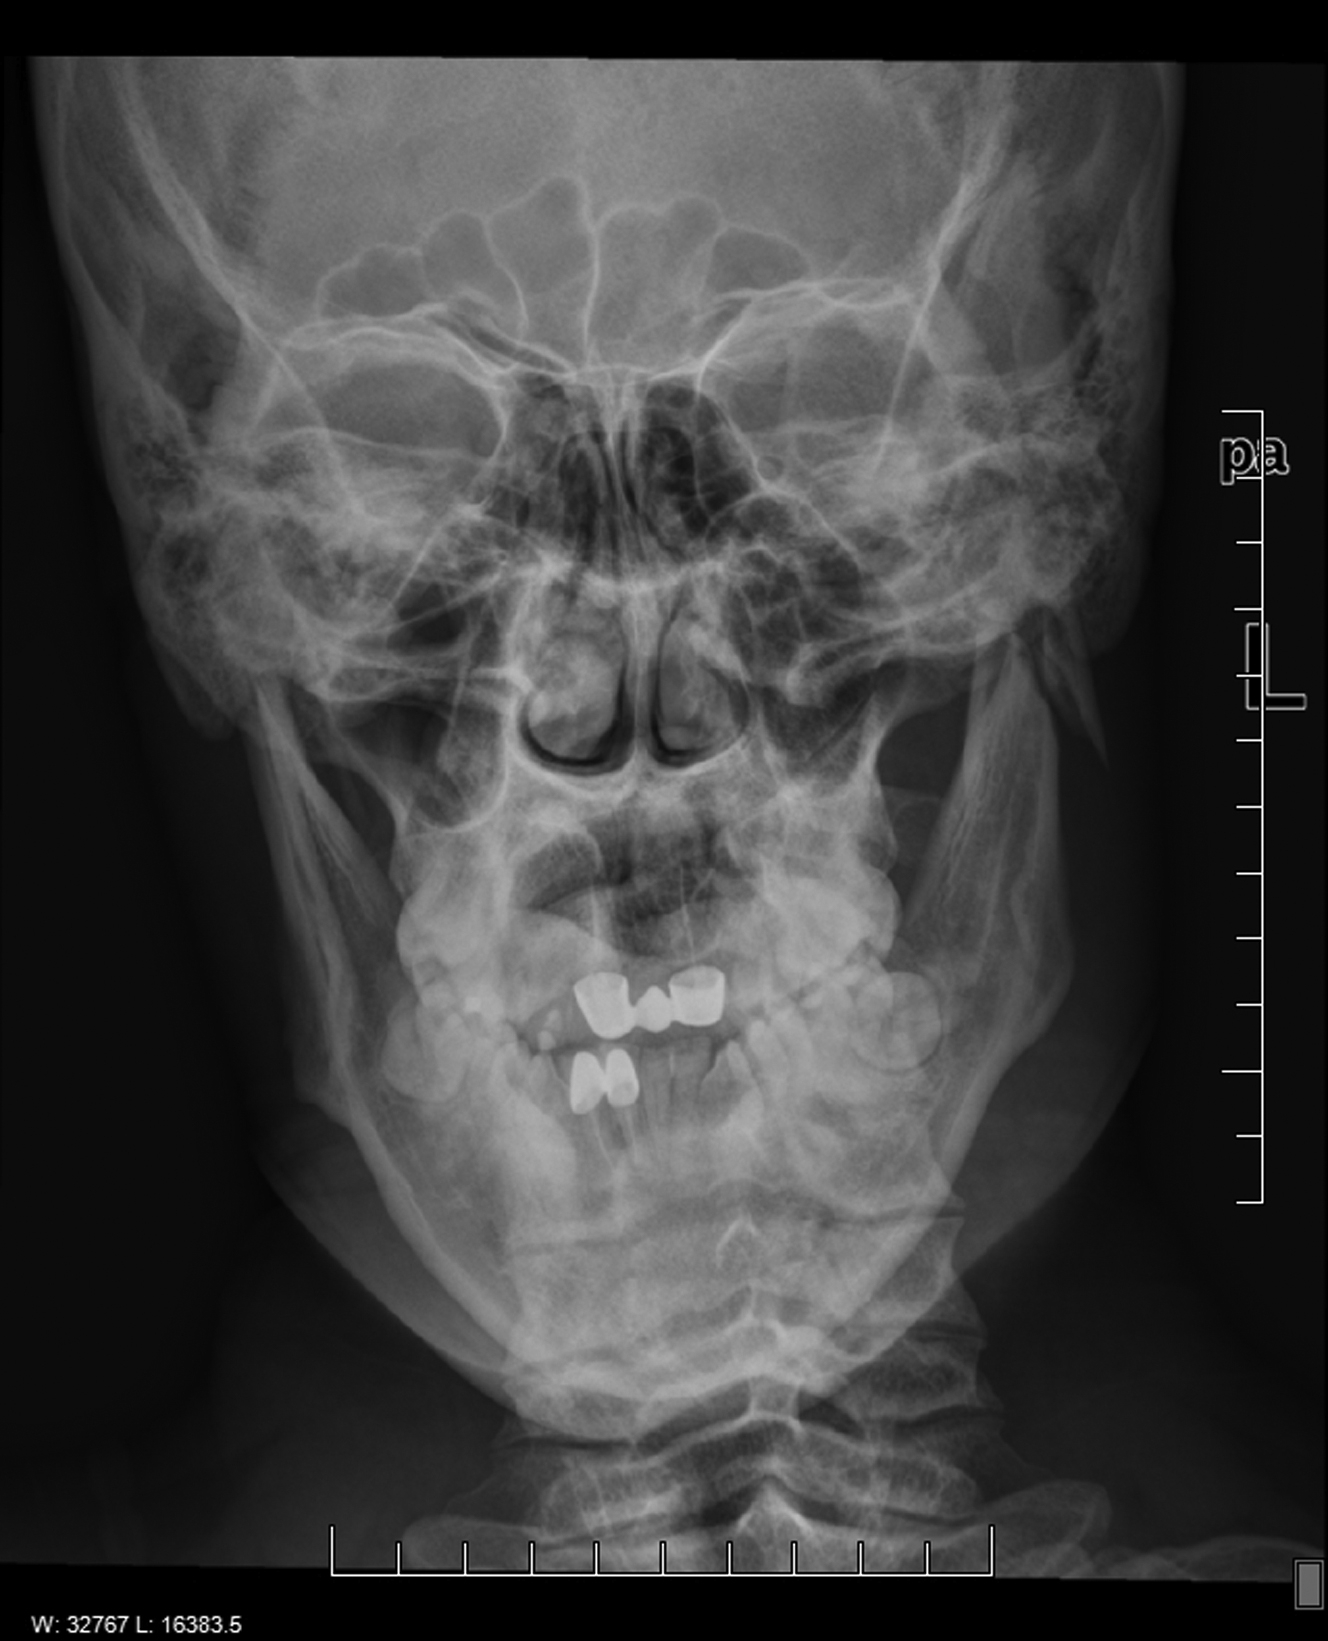

Helical computed tomography is the gold standard for radiographic diagnosis and can be reconstructed into 3-dimensional images. The mandible series is a set of plain x-rays taken from 5 different views ( Fig. 6 ). Towne’s view (patient has their head angled downward 30°), lateral oblique, and lateral views are best for visualizing the condyle. Panoramic orthopantomogram may also be obtained and provides a single composite panoramic image.